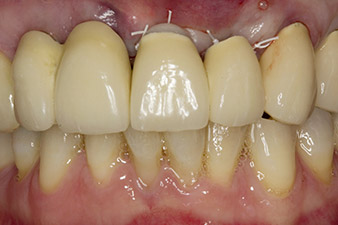

Situation nach Implantation und Augmentation

Abb. 6: Situation nach Implantation und Augmentation: Die alte Brücke wird für die Einheilphase wieder als Provisorium eingegliedert, mit frei geschliffenem Brückenglied an der Implantatposition 22. Als definitiver Ersatz ist eine Zirkonoxidbrücke von 12 auf das noch zu inserierende Implantat an Position 23 geplant.